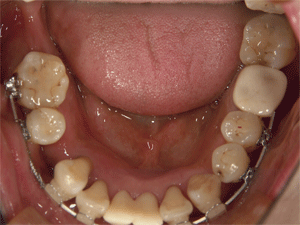

上顎左右第1小臼歯(犬歯の隣)の2本を抜歯しました

上顎第1大臼歯にはバンドを付けるため、青色のセパレートゴムを入れていきます。下顎も抜歯をして矯正していくのですが、まずは上顎から・・・

青色のゴムが歯間部分を広げ、バンドを入れるスペースを作ってくれます 矯正を希望してはこちらをクリック |